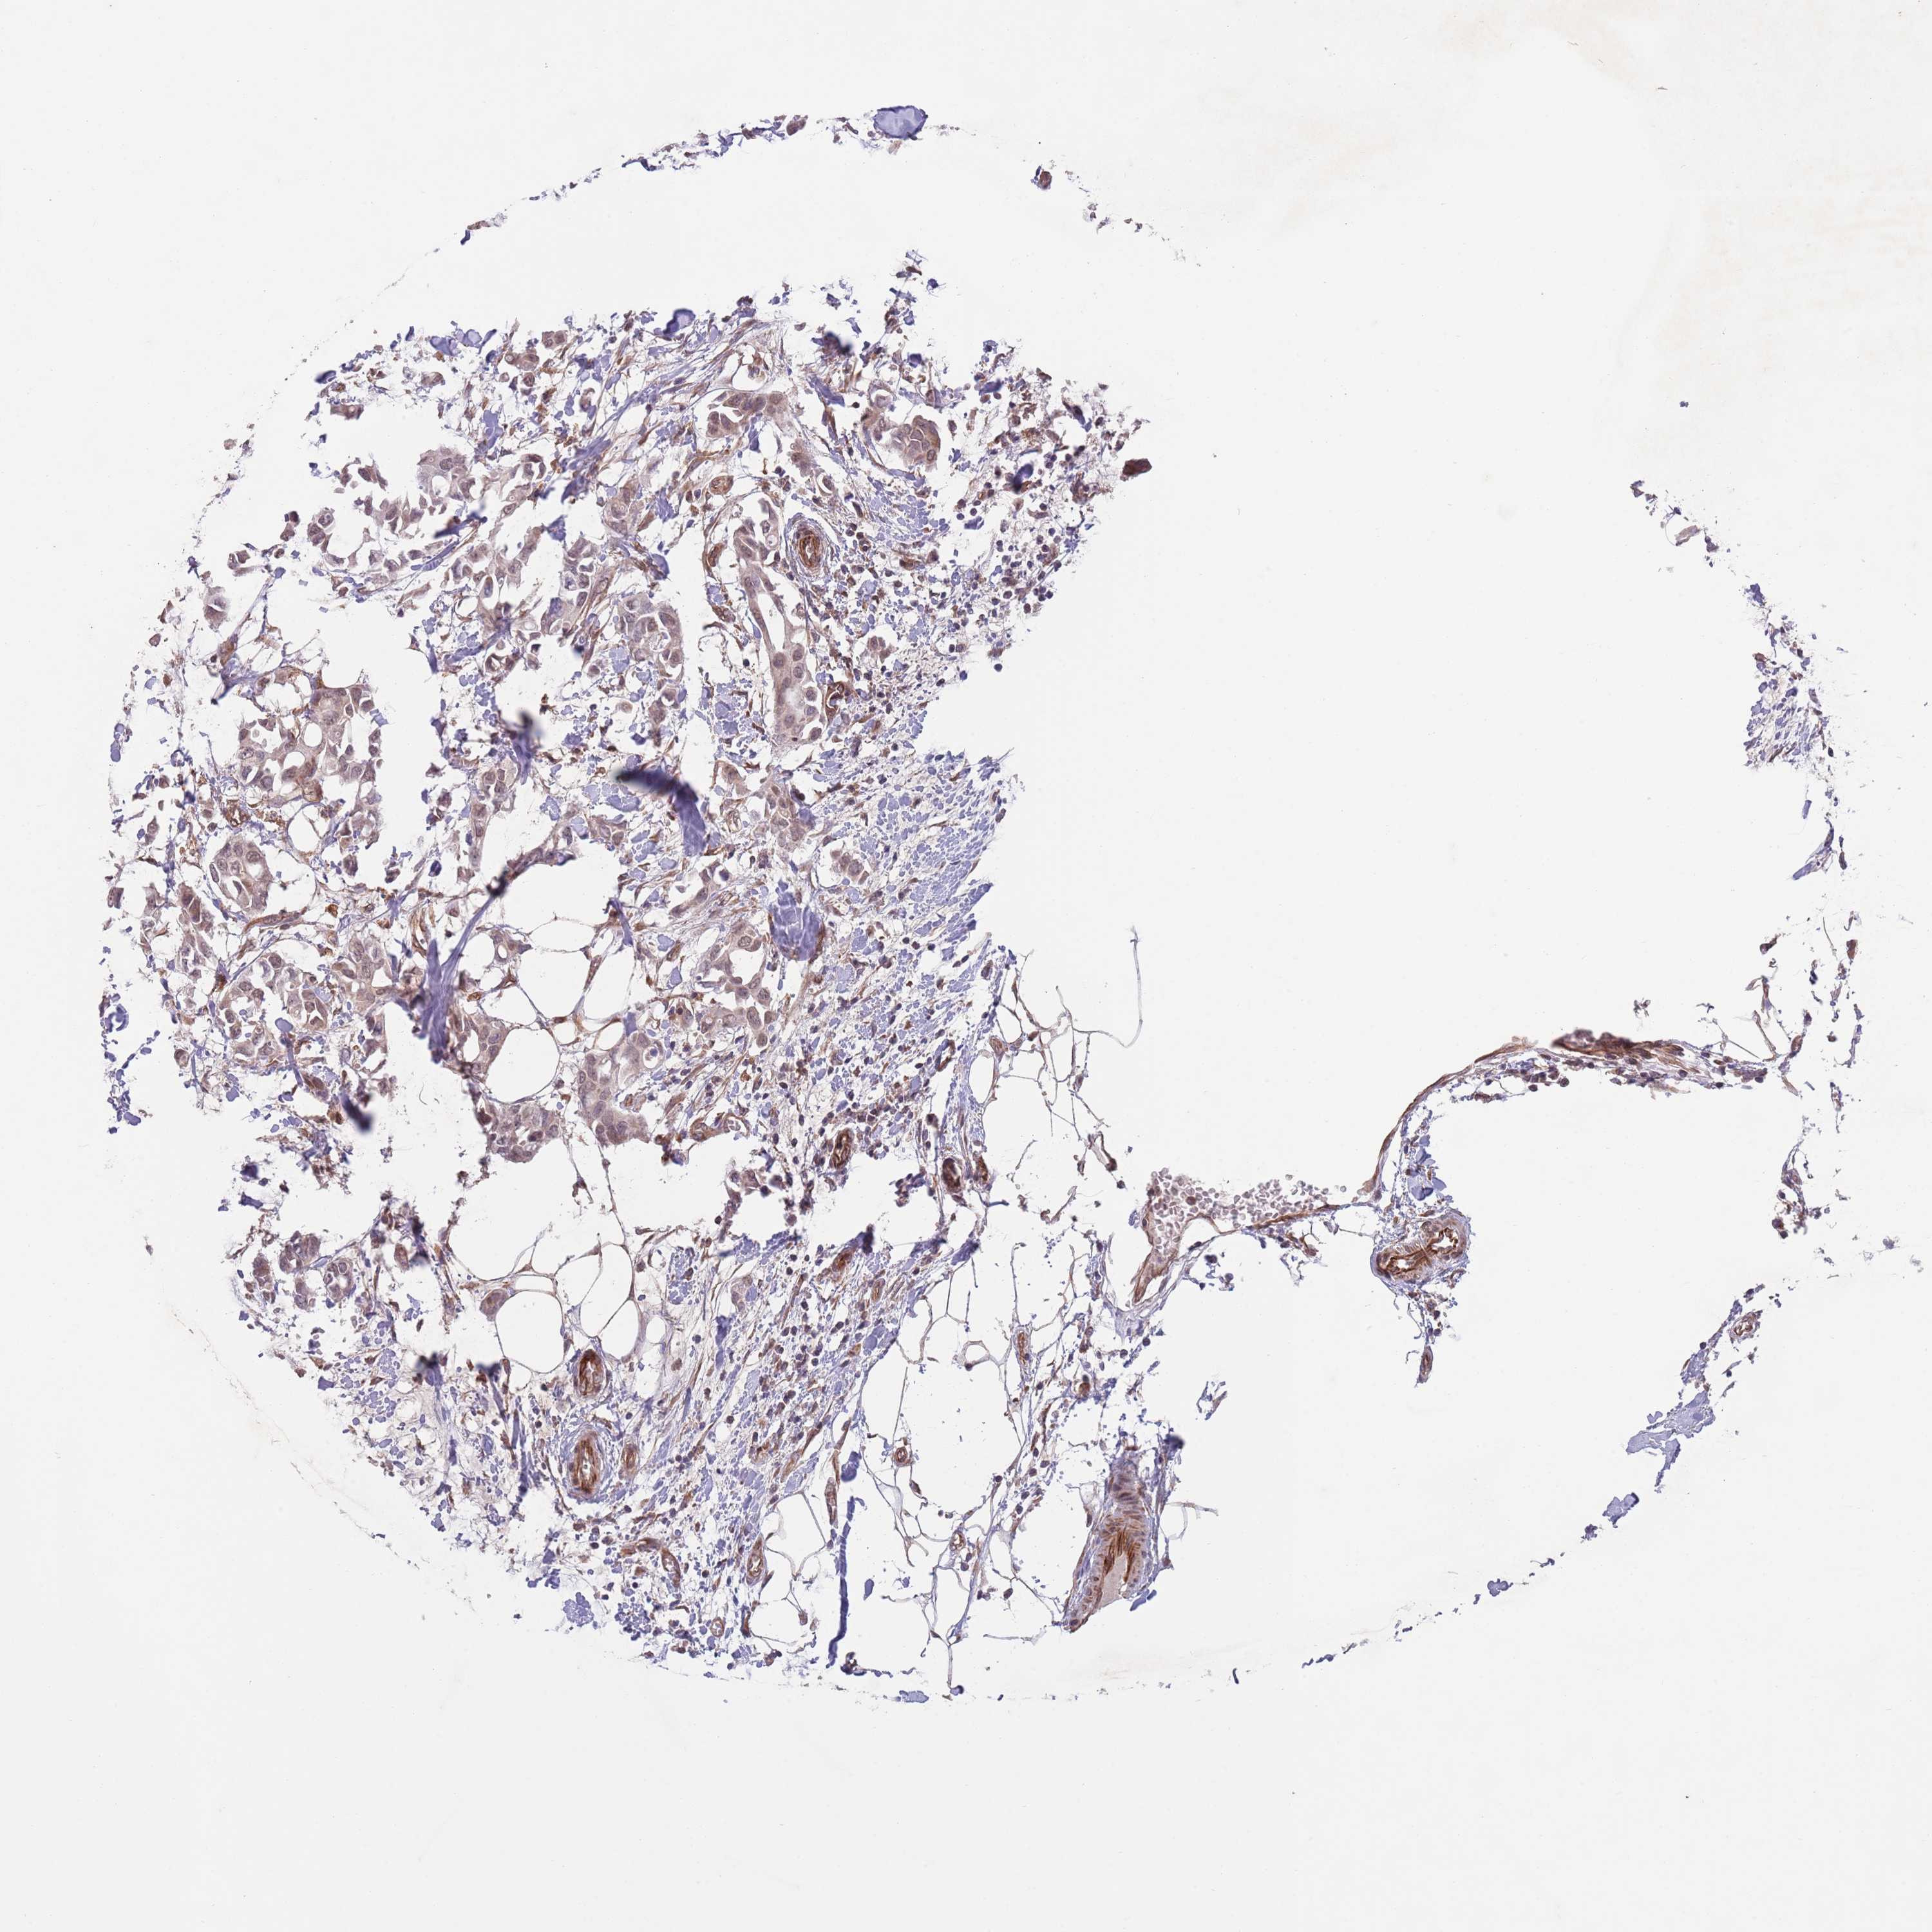

BRCA TCGA BRCA VALIDATION PROTEIN EXPRESSION

Breast cancer

Human cancer

Breast invasive carcinoma